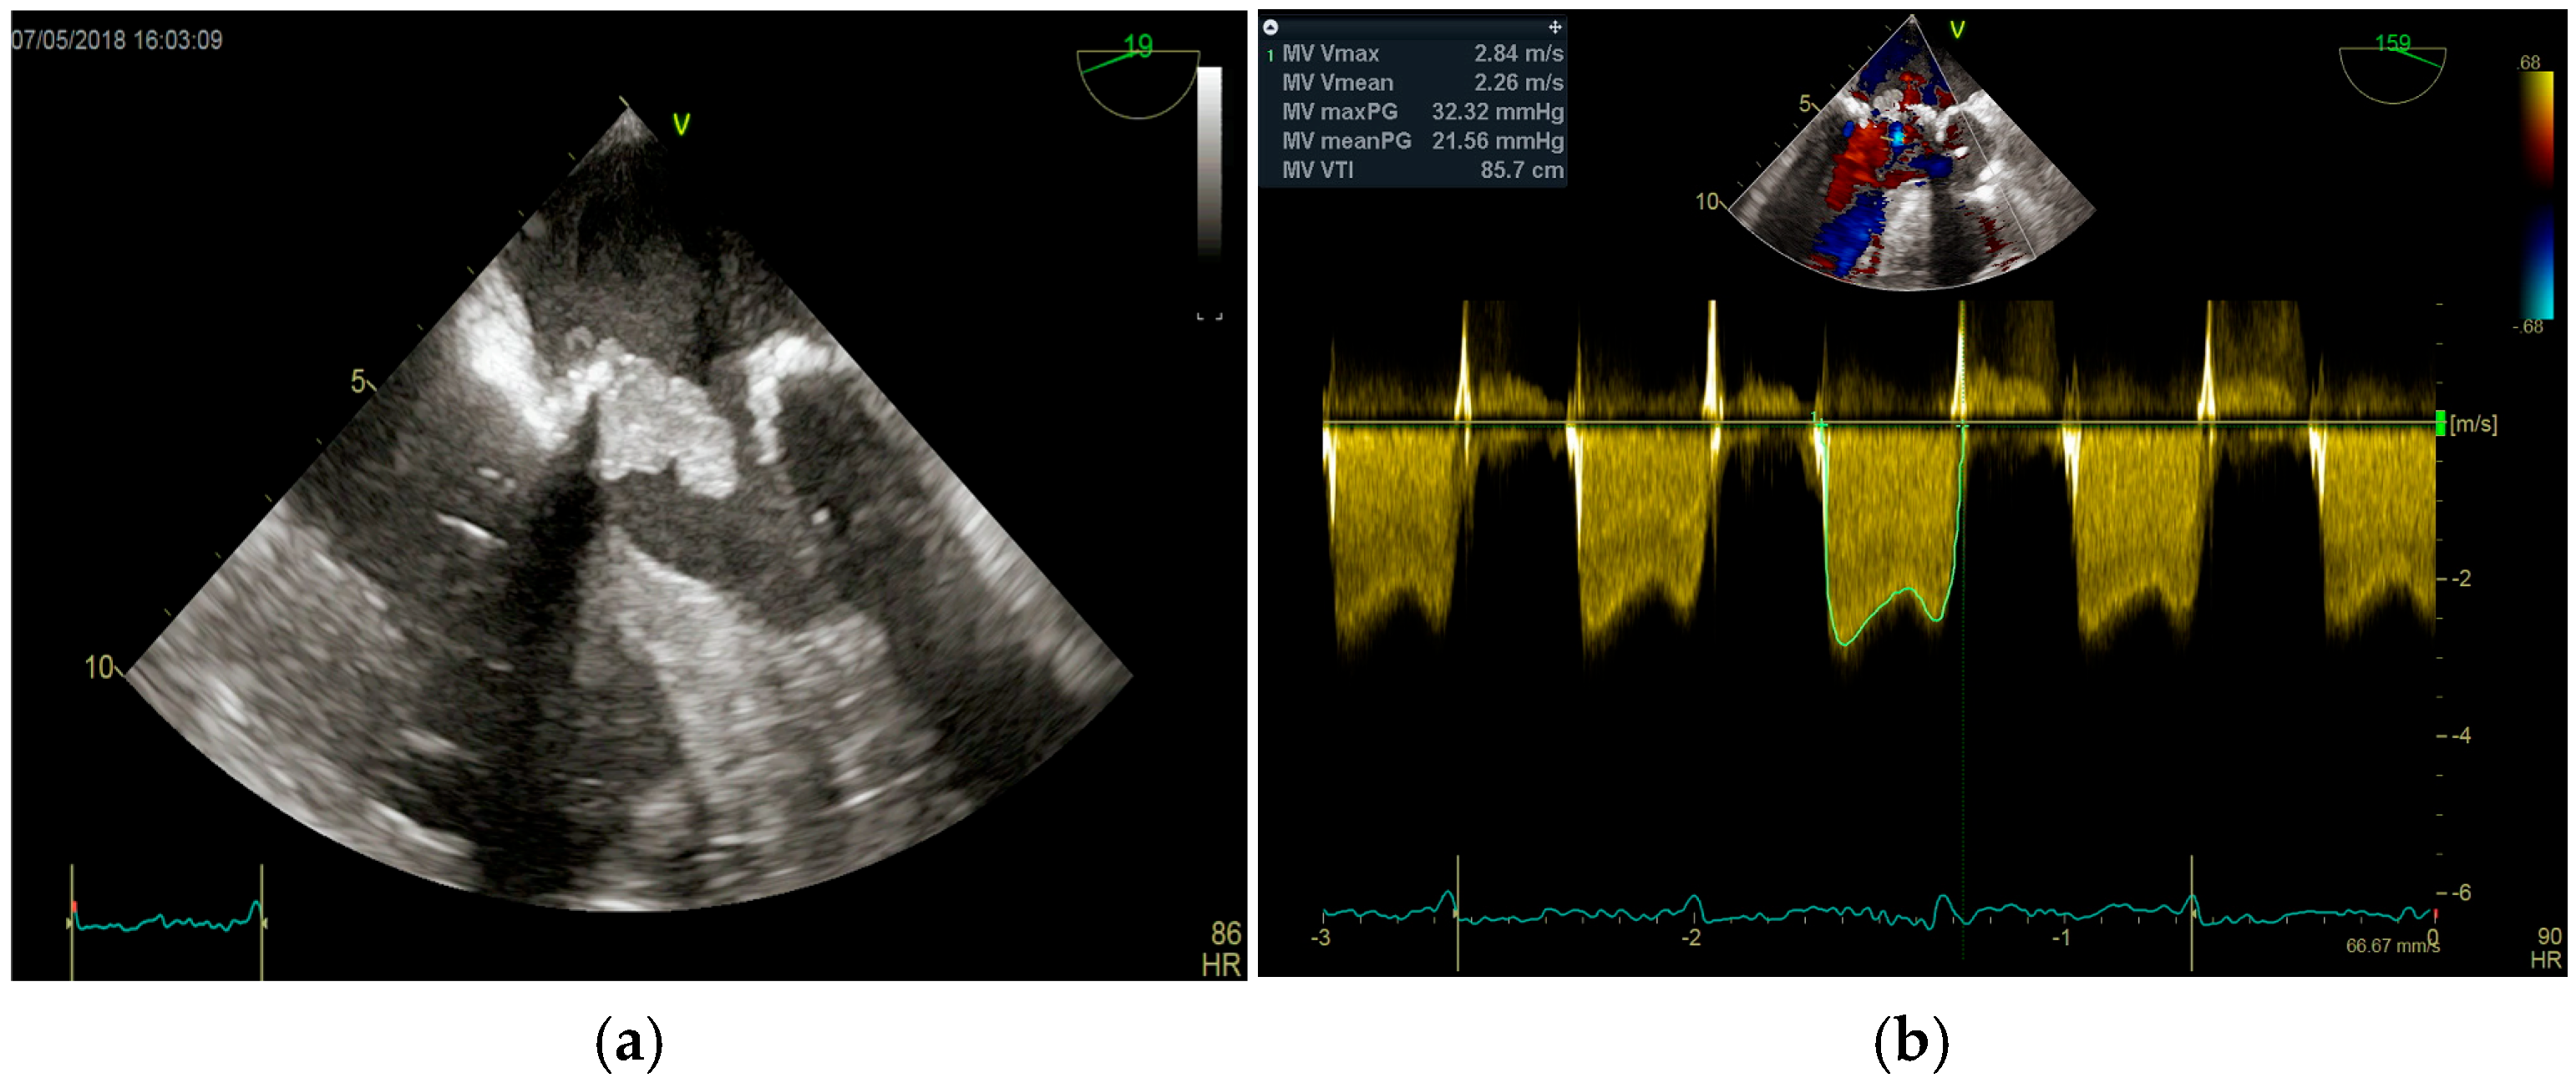

- valvular or leaflet perforation, i.e., tissue defects causing valvular regurgitation originating from the site of perforation.

- valvular aneurysm, a saccular outpouching of a valve leaflet, protruding into the atrium or ventricle.

- perivalvular or perigraft abscess, an echolucent or echodense area adjacent to the valve annulus or prosthetic ring often with irregular borders and sometimes with evidence of cavity formation.

- pseudoaneurysm, a contrast-filled outpouching with a narrow neck communicating with the cardiac lumen, often adjacent to the valve annulus. On echocardiography, it appears as a pulsatile cavity with systolic expansion and diastolic collapse.

- intracardiac fistula, visualized as an abnormal communication between cardiac chambers or vessels, is often detected by using color Doppler.

- significant new valvular regurgitation compared with previous imaging, i.e., increase in regurgitant jet size, vena contracta width…